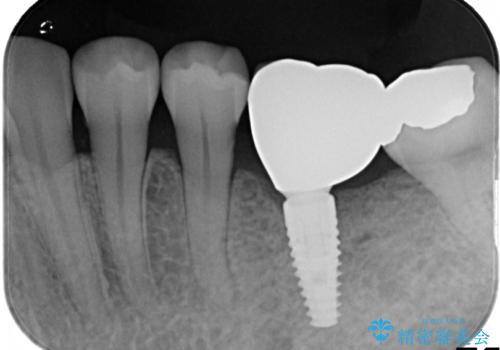

- Ⅲ度の分岐部病変をきたした第1大臼歯を抜去、待時しインプラントによる咬合回復を計画した。

インプラントの種類:strauman SLActive

かぶせ物の種類:Bellezza screw retain